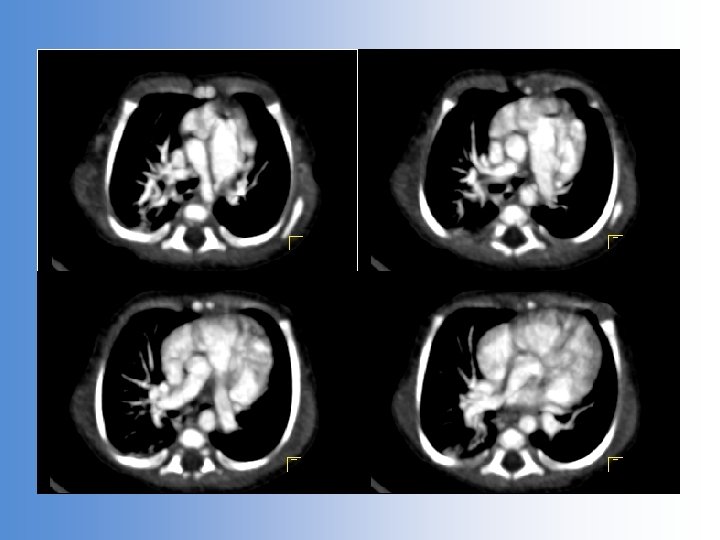

3 month old baby failure to thrive tachypnoea Echo: Anomalous RPA arising from aorta LA/LV volume loading LA/Ao ratio 2. 45 Severe TR PAS 78+5 mm. Hg

Anomalous RPA from aorta

The state of the pulmonary vasculature RPA pressures systemic supra-systemic Elevated LA pressures LPA bearing RV output Established PVOD